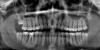

Pekarnik Опубликовано 10 мая, 2012 Поделиться Опубликовано 10 мая, 2012 2004 год - Удаление нервов и пломбировка каналов на нижней шестерке справа.2009 год - Во время профилактического осмотра и снимка на корне данного зуба обнаруженагранулема. Скорее всего из-за некачественной пломбировки. Зуб не беспокоит все эти годы. После совета на данном форуме, что гранулему нужно лечить даже если не беспокоит и от нефиг делать решаю залезть в зуб. Январь 2012 год - Доктор перепломбирует каналы. После лечения зуб периодически ноет.Май 2012 год - Болит в районе зуба. Прикладываю снимок в одном файле (Снимок.jpg)1- до лечения. 2- контрольный снимок после перепломбировки каналов ( после 2 недельной закладки лекарства)3- сейчас - спустя 4 месяца. + Орто до лечения. Вопросы:1. В чем может причина боли и что делать?2. Нормально ли то что сейчас на корне. Мне казалось что за 4 месяца гранулемы не должно остаться?3. Хороша ли методика постановки постоянной пломбы спустя 2 недели после закладки лекарства? Слышал, что кладут до 2 месяцев и наблюдает и только в случае положительного результата - ставят постоянную пломбу. Врач говорит что все ОК. Ссылка на комментарий

shishok Опубликовано 11 мая, 2012 Поделиться Опубликовано 11 мая, 2012 Медиальные каналы запломбированы не очень хорошо. Ссылка на комментарий

Magdalena Опубликовано 11 мая, 2012 Поделиться Опубликовано 11 мая, 2012 Медиальные каналы запломбированы не очень хорошо.+ 100. Зуб необходимо перелечивать, каналы у верхушки в корне, на котором гранулема, практически пустые. Ссылка на комментарий

Magdalena Опубликовано 13 мая, 2012 Поделиться Опубликовано 13 мая, 2012 (изменено) На мой взгляд на трещину не похоже - скорее всего это просто тень на снимке, трещину можно увидеть во время лечения, особенно при использовании микроскопа. То, что материал выведен за верхушку - это не показатель того, что канал запломбирован герметично на всю длину, а при отсутствии герметизма - есть место для жизнидеятельности микробов. Если хотите зуб сохранить - его нужно перелечивать. На последнем снимке есть признаки резорбции (разрушения) верхушки корня, единственный способ остановить данный процесс - это хорошо прочистить. промыть каналы, временно запломбировать пастой на основе гидроксида кальция на 2-3 недели, затем герметично запломбировать на всю длину каналы и сделать герметичную реставрацию зуба (восстановление внутрикорневой вкладкой и коронкой), иначе микробы будут попадать еще и из ротовой полости и опять начнется то же самое. Изменено 13 мая, 2012 пользователем Magdalena Ссылка на комментарий